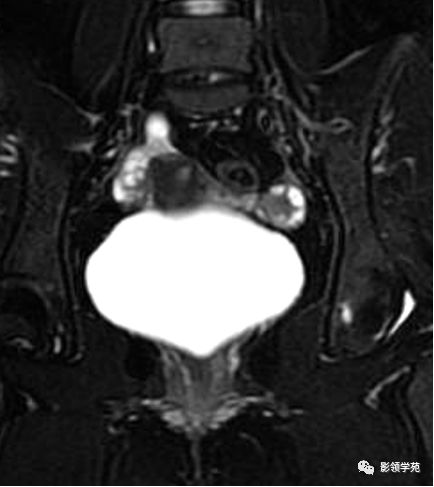

宫颈癌MRI表现

宫颈癌可表现为类圆形或不规则形肿块,在T2WI上表现为均匀或欠均匀的高信号,与正常宫颈基质及宫旁脂肪形成良好的自然对比。

- Ⅰ期肿瘤:侵犯宫颈基质,T2WI等信号肿块,宫颈管扩大及宫颈纤维基质中断

- Ⅱ期肿瘤:宫颈增大,宫旁肿块或宫旁脂肪组织内出现异常信号的粗线状影

- Ⅲ期肿瘤:侵犯至阴道下部,外延至盆壁,或出现肾积水。

- Ⅳ期肿瘤:膀胱壁或直肠壁低信号中断,膀胱壁或直肠壁增厚或腔内肿块。

DWI:局限性高信号,癌组织ADC值<癌旁组织<小于正常宫颈组织